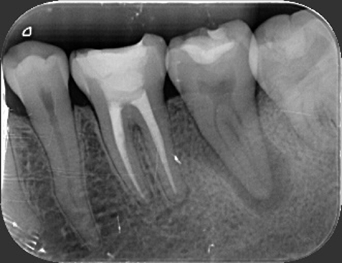

經 X 光與 CBCT 斷層影像評估後,牙髓病專科(根管專科)顏意欣醫師發現,這是一顆鈣化合併嚴重彎曲的根管。

這類狀況非常棘手——鈣化會封住根管開口、彎曲角度又大,若用傳統器械治療,極易發生器械斷裂或清潔不全。